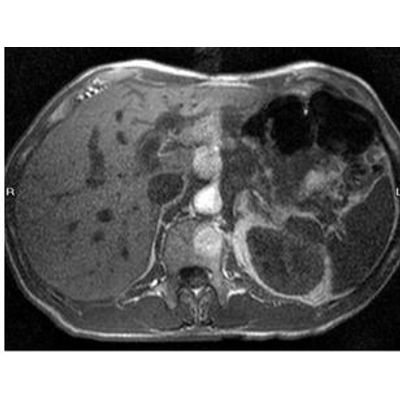

Mangoral is a novel oral imaging agent in development for use in MR-imaging of the liver. Mangoral aims to improve the detection and visualization of focal liver lesions (including liver metastases and primary tumors) in patients with severe kidney impairment. Mangoral is currently in Phase 3 development including the registration-enabling study, SPARKLE.

Early detection and localization of focal liver lesions is critical for optimal patient management. MR imaging with a contrast agent allows for more timely and targeted clinical decisions. This can improve life expectancy for patients with liver cancer or liver metastases.

Contrast agents enable the radiologist to distinguish normal from abnormal tissue, which in turn guides diagnosis, treatment decisions, monitoring and planning. This can ultimately improve a patient`s chances of survival. MRI in combination with a contrast agent is regarded as the most sensitive diagnostic method for liver imaging.

Mangoral, if approved by regulatory agencies, has the potential to be the standard of care for liver imaging of patients with impaired kidney function as it offers high quality imaging compared to an unenhanced MRI.